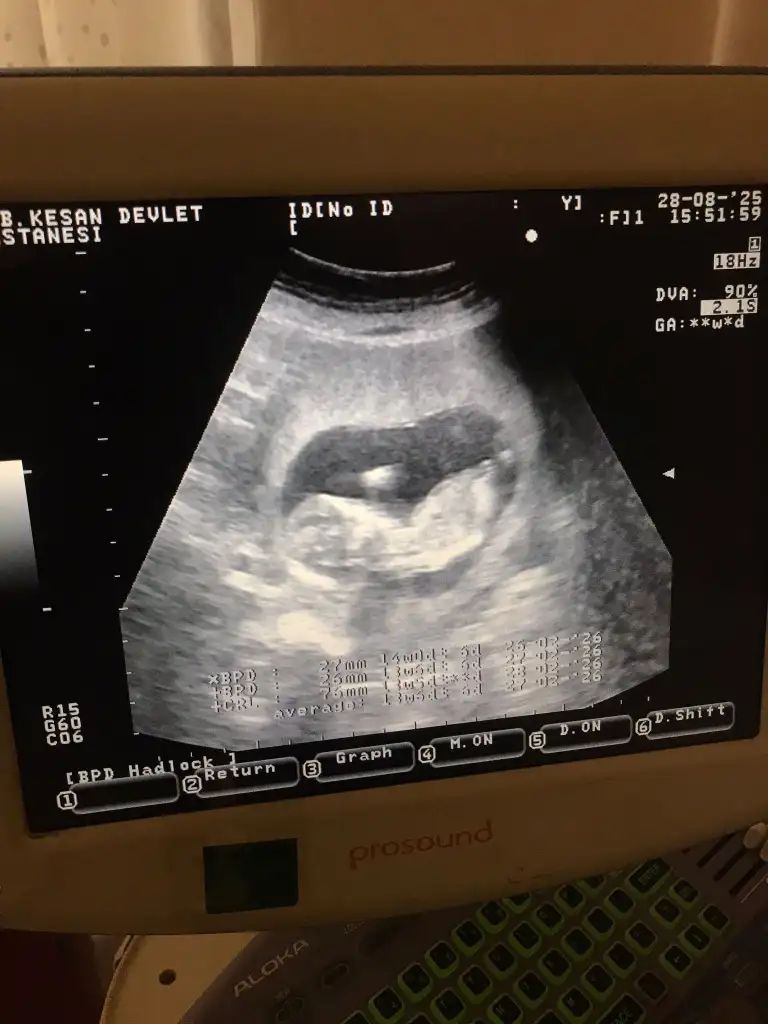

Bacım ikisinden biri işte, bu kadar önemli mi gerçekten?Konudan çok alakasız ama cinsiyet tahmini edebilirmisin ilk hamileliğimde merak ediyorum 14 haftalık Eki Görüntüle 3637518

Erkege benziyor ama zaten 16.haftada ogreniliyor cinsiyet, ultrasona girmeden once birazcik cikolata yemeni tavsiye ederim o zaman sıpalar hareketleniyor, donuyorlar. Sağlıcakla dogurun.Evet oda doğru

%50 erkek.Konudan çok alakasız ama cinsiyet tahmini edebilirmisin ilk hamileliğimde merak ediyorum 14 haftalık Eki Görüntüle 3637518